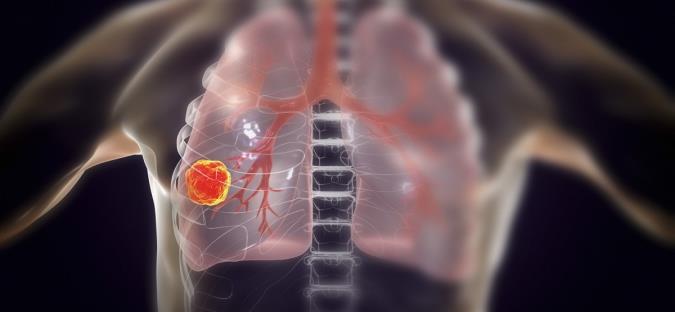

امروز سرطان ریه به دلایل گوناگون و بسیاری در میان بسیاری از افراد شیوع پیدا کرده است. این بیماری حاصل رشد و بیشتر شدن بیش از حد سلول های ریه می باشد. به طور کل بدن ما وظیفه دفع سلول های مرده را دارد و هر سلولی پس از این که مدت زمان خاصی را زندگی کرد می میرد و سلول های جدید جایگزین او میشود. اما در هنگامی که به دلایل مختلفی مانند عدم تعادل در سیستم مرگ و میر و رشد سلول ها ممکن است برخی از سلول ها نمیرند و تجمع بیش از حد سلول ها باعث ایجاد تومور در ناحیه ریه و در نتیجه سرطان ریه میشود که میتواند مشکلات زیادی را برای افراد به وجود بیاورد. اما دلیل اصلی سرطان ریه بیش از حد شدن مقدار سلول های مرده در یک بخش از سرطان ریه است که باعث ایجاد بافت های سفت تر نسبت به سایر نقاط ریه و در نهایت ایجاد تومور و سرطان ریه می شود. این بیماری علائم و درمان های خاصی دارد که ما در ادامه سعی نمودیم که به بررسی این علائم و درمان ها برای شما بپردازیم تا خدایی نکرده اگر دچار این بیماری هستید آن را سریع تر تشخیص دهید و به پزشک مراجعه نمایید تا درمان خود را شروع نمایید و به زندگی سالم خودتان باز گردید. جالب است بدانید که پیش از هزار نهصد و سی سرطان ریه اصلاً معمول نبود و یک نفر از هزار نفر به این بیماری دچار می شد. اما پس از دهه هزار نهصد و سی و تولید انواع مختلف دخانیات و مصرف بی رویه دخانیات باعث شد که سرطان ریه به یکی از شایع ترین بیماری های آن دوره تبدیل شود.

امروزه سرطان ریه یکی از کشنده ترین سرطان ها در میان زنان و مردان در جهان میباشد که هرساله جان بسیاری از افراد را میگیرد. متاسفانه سرطان ریه پس از ابتلاء به سرعت گسترش پیدا میکند و به سایر نقاط بدن مراجعه میکنند. در نتیجه این سرطان یکی از خطرناک ترین سرطان ها می باشد که نقاط مختلفی مانند مغز استخوان، غدد فوق کلیه، و کبد را درگیر میکند و باعث آسیب رسیدن به این نواحی نیز میشود. توجه نمک افرادی که سیگاری هستند و دخانیات استعمال می کنند بسیار در معرض ابتلا به این سرطان می باشد. همچنین افرادی که به صورت منفعل سیگار میکشند یعنی در کنار افرادی که سیگاری هستند زندگی میکنند، نیز خطر ابتلا به این بیماری را تا درصد بسیار بالایی دارند. اما توجه نمایید که ترک سیگار میتواند در عدم ابتلا شما به این بیماری کاملاً مؤثر باشد و خطر ابتلای شما را به این بیماری تا حد بسیار زیادی پایین می آورد. یکی از نکاتی که بسیار دردناک می باشد این است که تشخیص سرطان ریه در مراحل اولیه بیماری می تواند روند درمانی بیمار را سریع تر و راحت تر کند اما متاسفانه این بیماری در مراحل اولیه نمیتواند به راحتی تشخیص داده شود و معمولاً با انواع مختلف بیماری های دیگر مانند عفونت های تنفسی اشتباه گرفته میشود و گاهی فرد حتی هیچ گونه علائمی ندارد به همین دلیل این بیماری یک بیماری خاموش و خطرناک می باشد. در بیمارانی که به سرطان ریه مبتلا هستند و فقط ریه آن ها درگیر شده است احتمال زنده ماندن بیمار برای پنج سال پنجاه و چهار درصد می باشد. اما در افرادی که این بیماری به نواحی دیگر بدن آن ها نیز اما انتقال پیدا کرده باشد شانس بقای پنج سال او حدود چهار درصد می باشد. اما علائم این بیماری میتوانند شامل تنگی نفس، درد در ناحیه قفسه سینه، سرفه خونی، و درد در سایر نواحی بدنشان شود. شما میتوانید در صورت داشتن این علائم بیماری خود را تشخیص دهید.